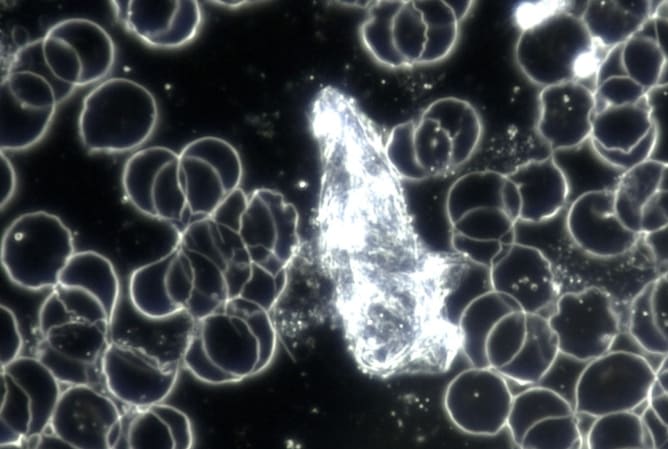

La microscope à fond noir est un outil avec lequel on observe une goutte de sang fraîche (prise au bout du doigt), sans la colorer, grâce à un éclairage particulier. Cela permet de voir les cellules vivantes telles qu’elles sont. Ce type d’examen donne une idée générale de la santé, peut montrer la présence de certains micro-organismes, révéler si les globules rouges ont une forme anormale (ce qui peut indiquer un manque de nutriments), et parfois détecter des signes d’infections bactériennes ou fongiques. C’est un outil génial pour orienter le diagnostic des troubles dont souffrent les patient-es et pour toutes celles et ceux qui souhaitent améliorer leur santé!